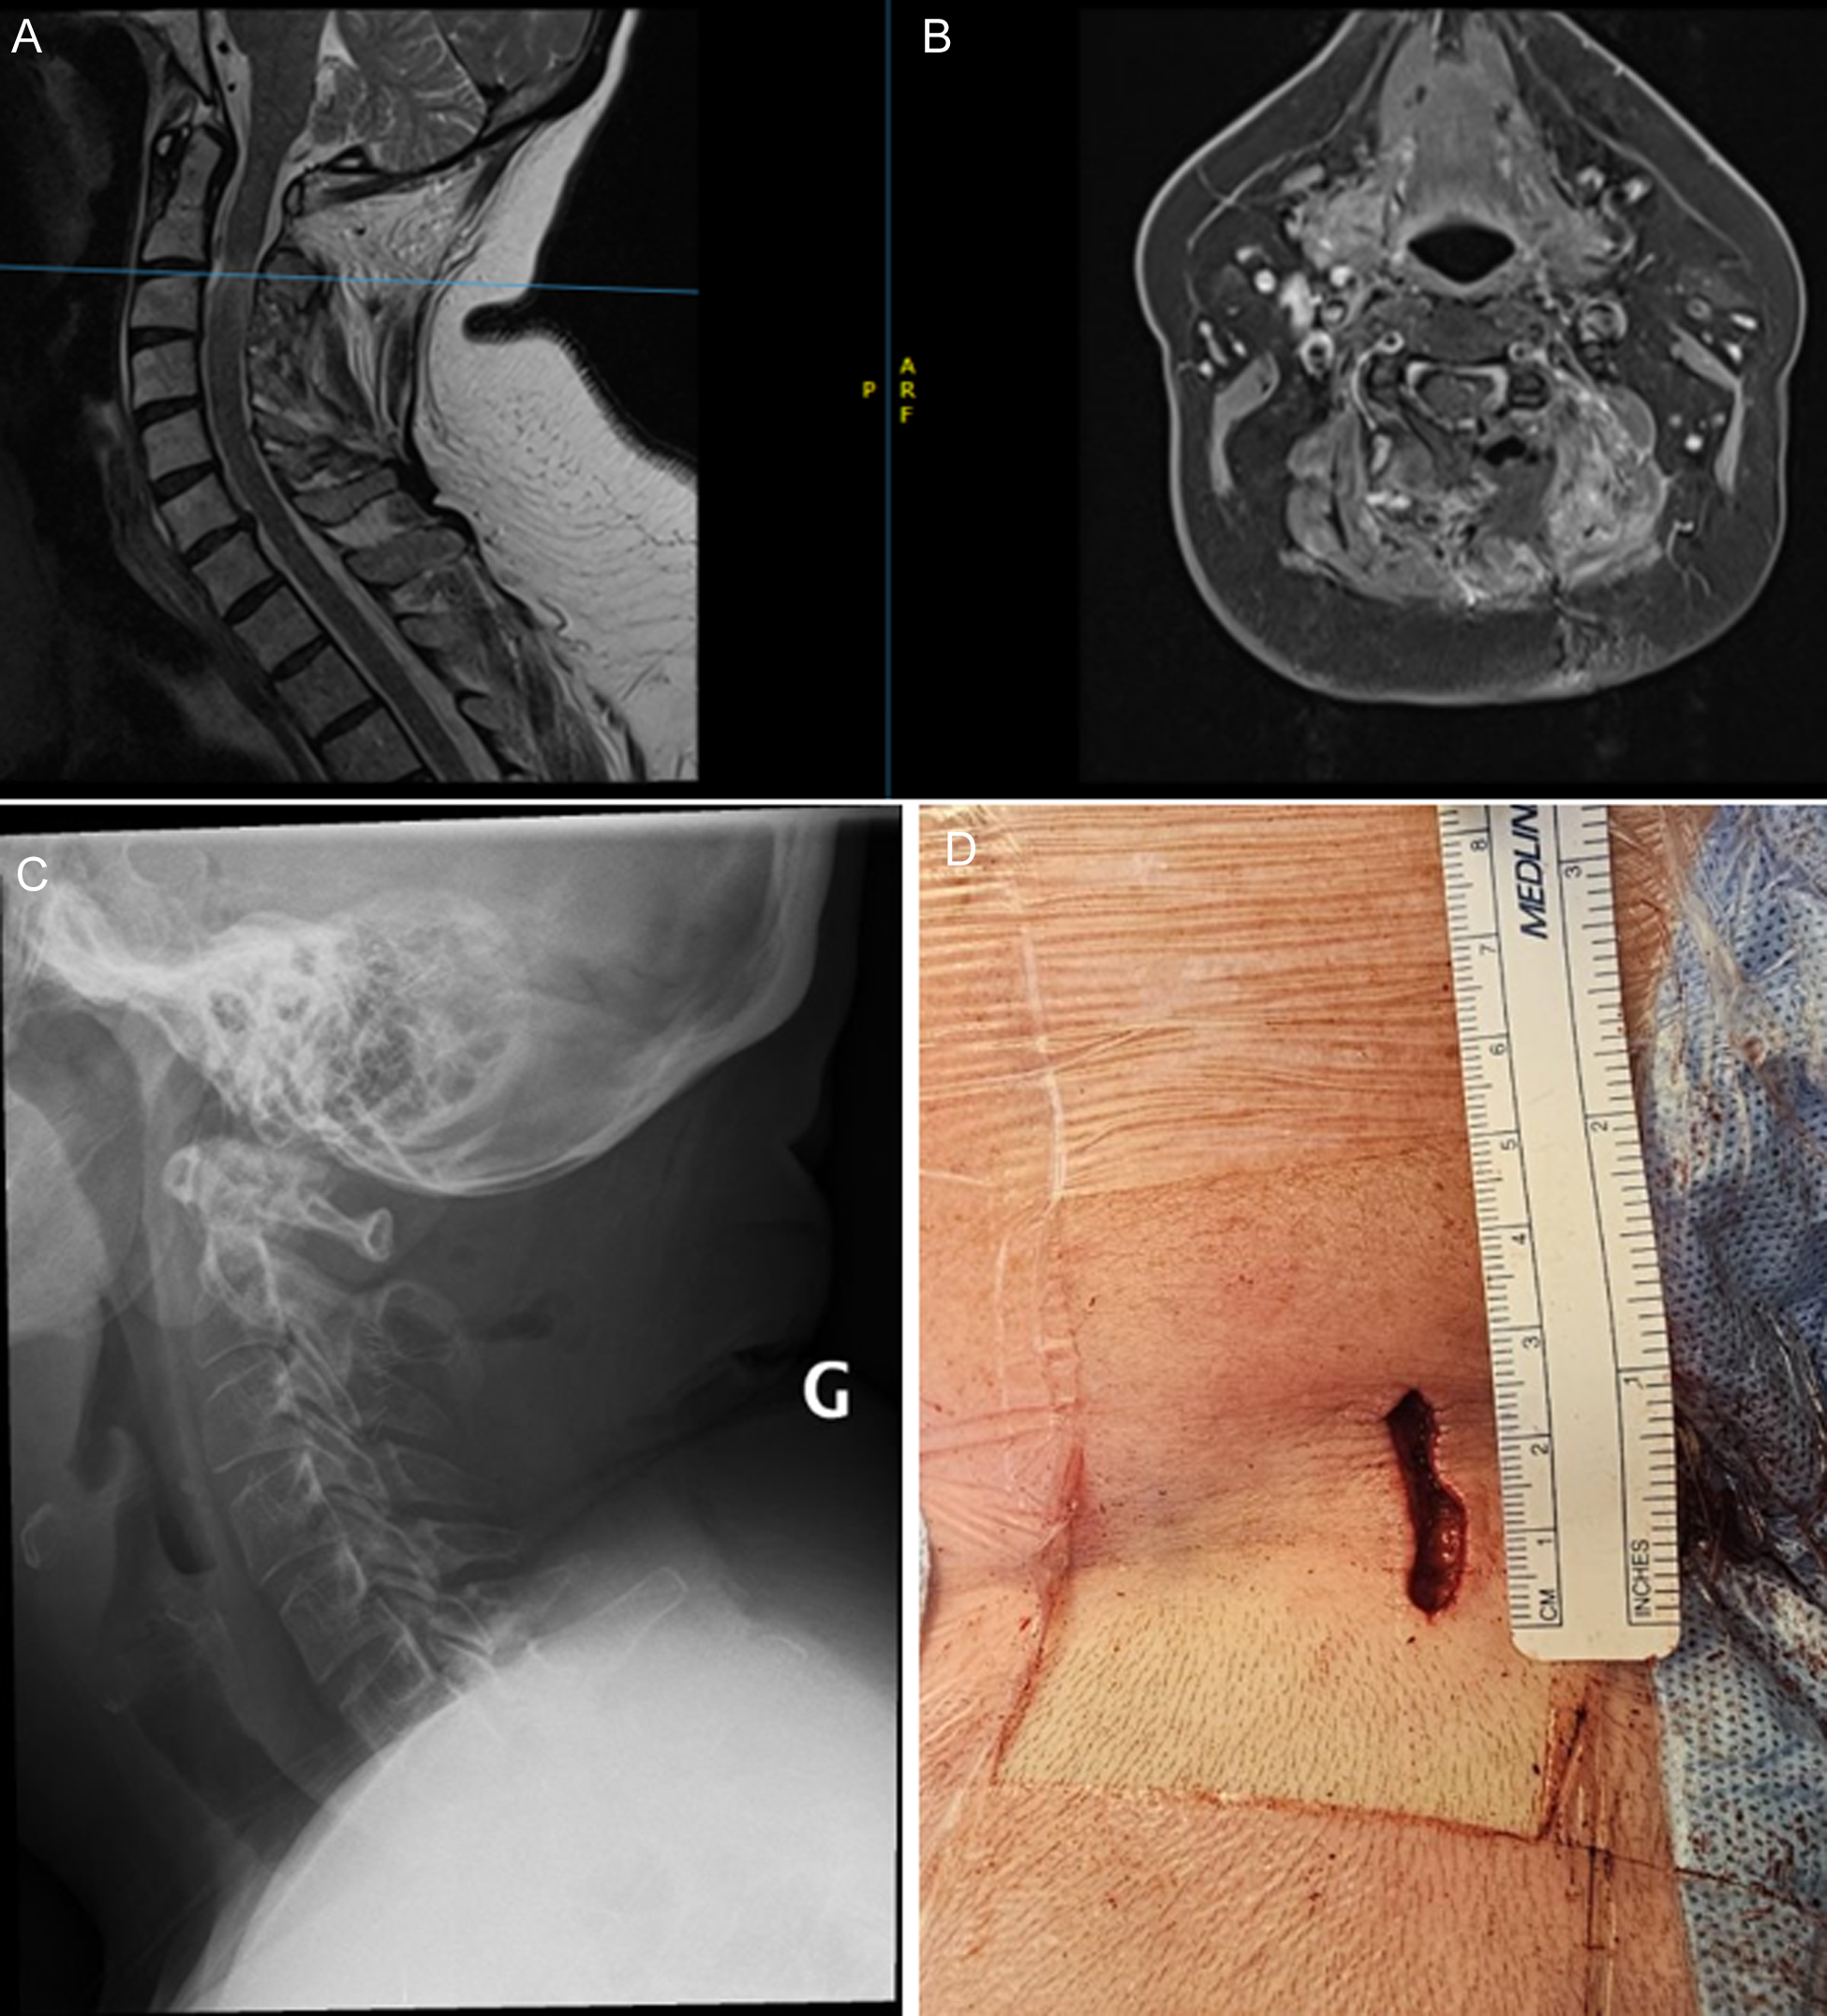

A 56-year-old female presented to our department with left upper extremity neuropathic pain accompanied by left-sided weakness (Table 3). Imaging revealed C2 – C3 lesion with a craniocaudal diameter of 2.9 cm (Figure 2). Intraoperative bony resection, dural opening and tumour exposure are illustrated in Figure 3. Surgery was performed as described in the Methods section. Intraoperative neuromonitoring confirmed proper neurological function. Post-operative imaging confirmed GTR, adequate spinal cord decompression with preserved joint integrity and spinal stability (Figure 4). The patient experienced no surgical complications and was discharged home on post-operative day 2. At 12-month follow-up, no tumour recurrence was reported (Table 4).

Figure 4. Patient 1 post-operative imaging. (A) Sagittal T2 MRI and (B) Axial T2 MRI showing complete spinal cord decompression. (C) Post-op X-ray showing preserved spinal alignment. (D) Post-operative surgical corridor measuring 2.6 cm. Image obtained with permission from the patient.